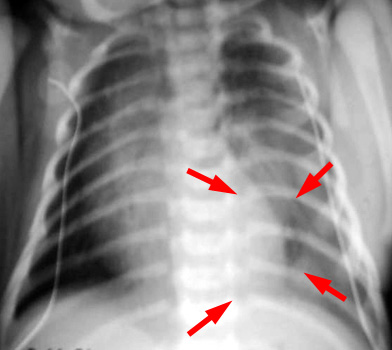

Extralobar sequestration is contained in its own separate pleura and commonly presents in the neonatal period with respiratory distress from mass effect. Furthermore, other anomalies are frequently found with extralobar sequestration. As with intralobar sequestration, extralobar sequestration is frequently found in the medial left lower lobe presenting as a soft tissue mass. Extralobar sequestration can be confused with an adrenal mass (neuroblastoma) because it presents as a mass in the medial left lower lobe.

Neonatal CXR demonstrates a mass in the medial left lower lobe. An MRI demonstrated a systemic arterial supply off the aorta which confirmed an extralobar sequestration.